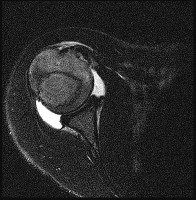

Figures 1 through 3 are the MRI scans of a 56-year-old woman in good health who reports a 6-month history of shoulder pain and external rotation weakness. Her radiographs are unremarkable. What is the diagnosis?

The images reveal T2-weighted MRI sequences with edema isolated to the infraspinatus. In the absence of a tear in the infraspinatus tendon, the edema is most likely due to compression of the suprascapular nerve in the spinoglenoid notch. As this pathology persists, progressive muscle atrophy and fatty infiltration can result. Compression of the suprascapular nerve in the suprascapular notch would have resulted in edema and weakness in both the supra- and infraspinatus muscles. Compression is commonly caused by cysts from the joint secondary to labral tears. A rotator cuff tear of the infraspinatus is not identified on these images, and there is no history of trauma provided. There is no evidence of an anteroinferior labral tear, nor would this be expected to result in external rotation weakness or MRI abnormality of the infraspinatus. Quadrilateral space syndrome results in compression of the axillary nerve, which supplies the teres minor.